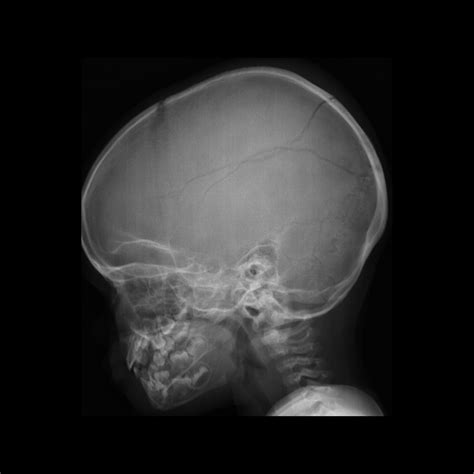

Understanding the intricacies of a Baby Skull Xray is crucial for healthcare professionals, especially those involved in pediatric care. This diagnostic tool provides valuable insights into the development and health of a baby's skull, helping to identify potential issues early on. This post delves into the significance, process, and interpretation of Baby Skull Xray images, offering a comprehensive guide for both medical professionals and curious parents.

A Baby Skull Xray is a radiographic imaging technique used to visualize the bones of a baby's skull. This non-invasive procedure is essential for diagnosing various conditions, including fractures, deformities, and developmental abnormalities. The X-ray images provide a detailed view of the skull's structure, helping healthcare providers make informed decisions about treatment and care.

Interpreting Baby Skull Xray results requires a trained eye and a deep understanding of pediatric anatomy. Here are some key points to consider:

• Bone Density: The density of the bones can indicate the presence of fractures or other abnormalities.

• Skull Shape: The shape of the skull can provide insights into developmental issues or deformities.

• Fontanelles: The soft spots on a baby’s skull, known as fontanelles, should be checked for proper closure and any signs of swelling or bulging.

• Sutures: The sutures, or the fibrous joints between the skull bones, should be examined for any signs of premature fusion or separation.